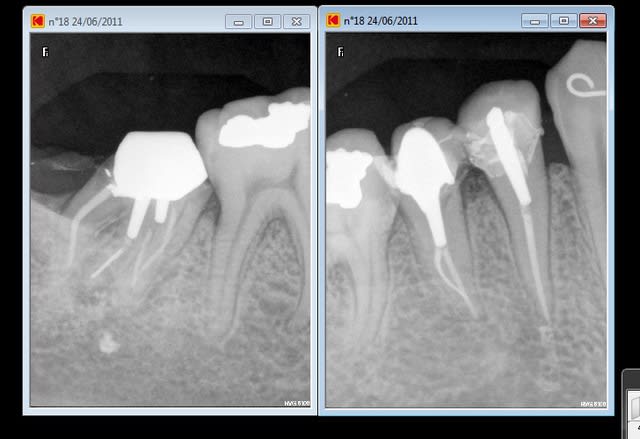

une ptite 38 de l'après midi (sans digue o pas bien fouilla !) mais j'avais oublié de faire la rétro avant dépose de la capote

en numéro deux radio d'une patiente qui s'était barrée avec mes endos et des inlays cores et qui revient 5 ans après ! je me 'en souvenais plus et je m'étais bien fait rire sur celles la( hero 6 4 2 je crois à l'époque)

tu l'as vu dans le canal distal le fragment de l'hero

chui fainéant : pas mis la digue car il aurait fallu reconstituer cette dent avant

mais bon à quatre mains on a mal travaillé dans un premier temps et pi on s'est rattrapés.

pas tentés par le MTWO ???